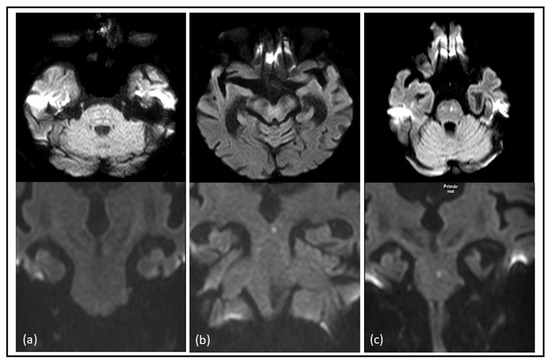

In nine cases (6.7%), the ischemic lesion was solely detected on axial DWI with one located in the midbrain and eight in the pons. Additionally, in eight cases (6%), comprising four in the midbrain, two in the pons, and two in the medulla oblongata, the ischemic lesion was exclusively identified on coronal DWI (refer to Figure 2 and Table 3).

Figure 2. Comparative identification of acute ischemic brainstem stroke on axial and coronal DWI: examples of diffusion-restricted lesions in the brainstem were more easily identifiable on axial diffusion-weighted imaging (DWI) compared to coronal DWI in the pons (a), acute diffusion-restricted lesions in the brainstem were more easily identifiable on coronal DWI compared to axial DWI in the mesencephalon (b) and diffusion-restricted lesions in the pons were identifiable on both axial and coronal diffusion-weighted imaging (DWI) (c).